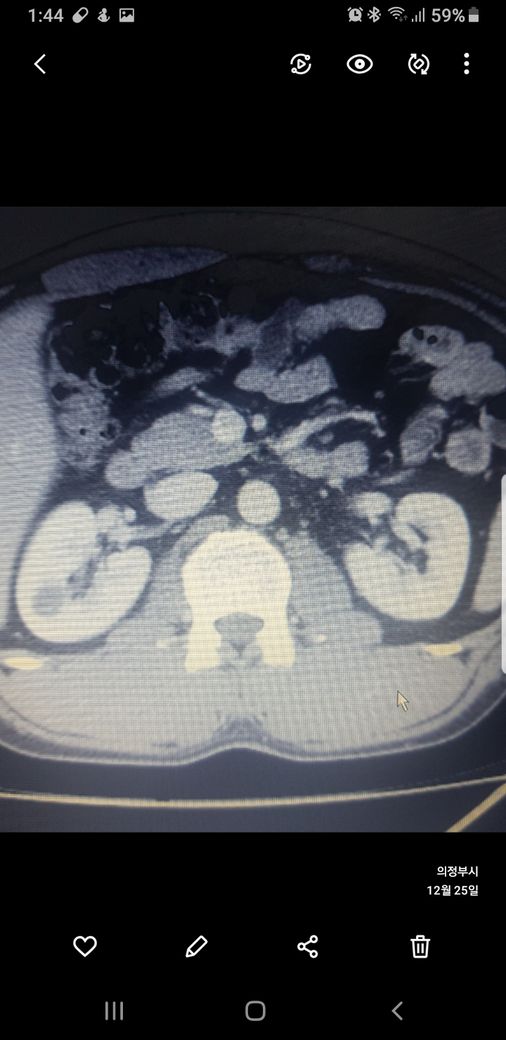

복부ct 작년 11월 , 올해 12월 촬영분입니다.

우측신장에 작년에는 1.7cm 물혹이 올해는 같은곳에 1.2cm 출혈성낭종이라는데

사진 1~4번째 는 작년

둘다 같은 병변이고 비조영증강에서 약간의 고음영 소견이 있어 출혈성 낭종이 의심됩니다.

신장의 낭성병변의 분류에서 1, 2, 2F, 3, 4이렇게 나뉘는데, 2에 해당되는 소견입니다.